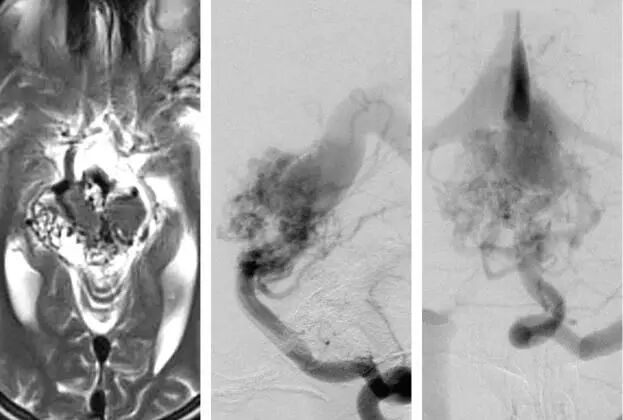

图7:图示一个未手术的包绕中脑的环状AVM。注意椎动脉造影的侧位与前后位显示的静脉引流系统。